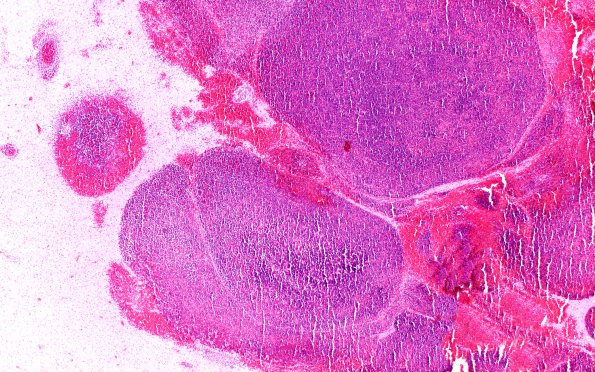

Washington University Experience | NEOPLASMS (HEMATOLYMPHOID) | Granulocytic Sarcoma | 1B2 Case 1 E 4X

1B2-4 Progressively increasing magnification of the constituent elements of leukemic nodules showing aggregates of myeloblasts, many with granular cytoplasm. (H&E)